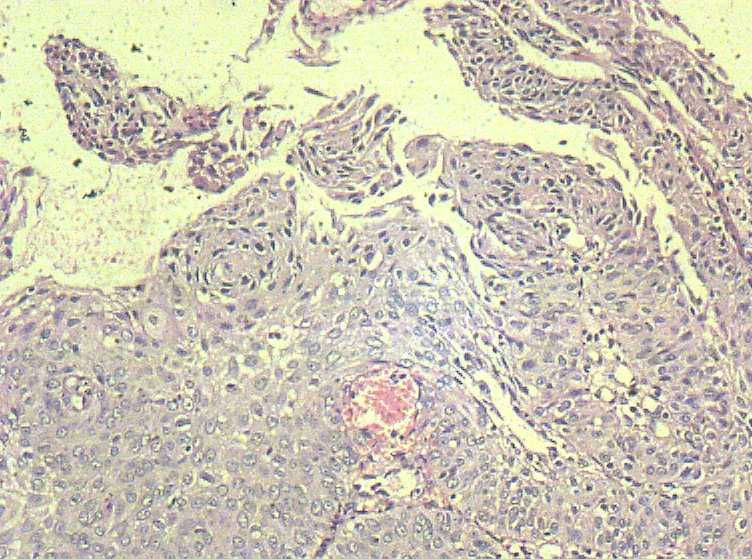

33岁 宫颈刮片看上去很像腺上皮病变,报了AGC 建议活检。 活检取自宫颈,图片如下:请帮忙看下,谢谢!

鳞状上皮增厚,乳头状增生,并见挖空样细胞。提示HPV感染。

有不典型增生, 不知道大家有没有看到。  如果有不典型和上面的图像可或直接报 :尖锐湿疣伴不典型增生。